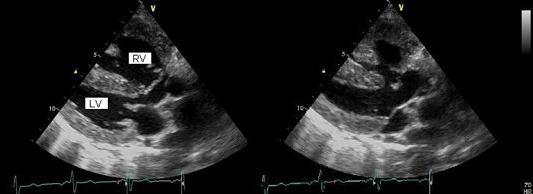

図2: 心エコー長軸像、拡張期(左)と収縮期(右)に大動脈弁直下の高い位置に心室中隔欠損を認める。

そのため、大動脈は心室中隔に騎乗し左室と右室から血流を受ける。